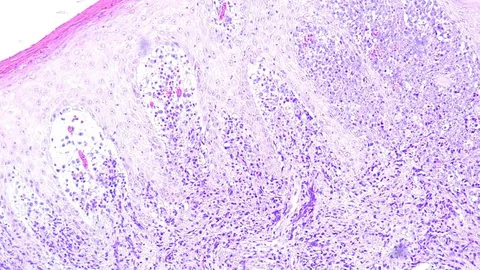

Breast cancer develops when cells in the breast tissue begin to grow uncontrollably, forming a malignant tumor. This growth is often driven by hormones, genetic mutations and environmental factors. One of the key players in breast cancer development is estrogen, a hormone that can fuel tumor growth. Factors like chronic inflammation and metabolic dysregulation also contribute to the progression of the disease.